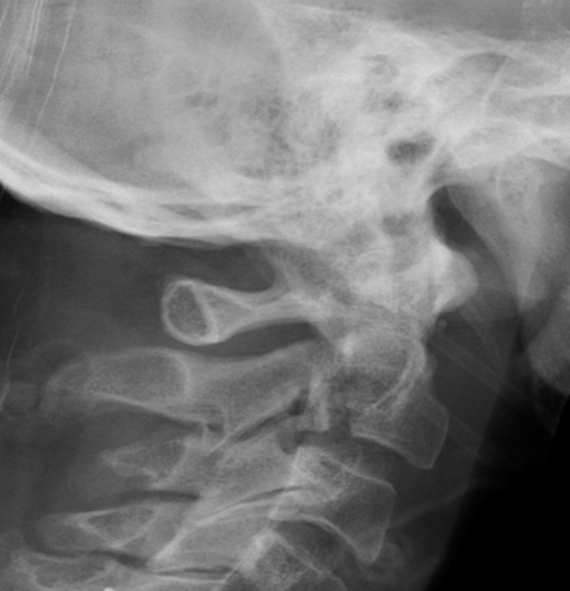

Hangman's fracture reduced and held in halo-vest

Post halo flexion and extension views demonstrating fracture stability